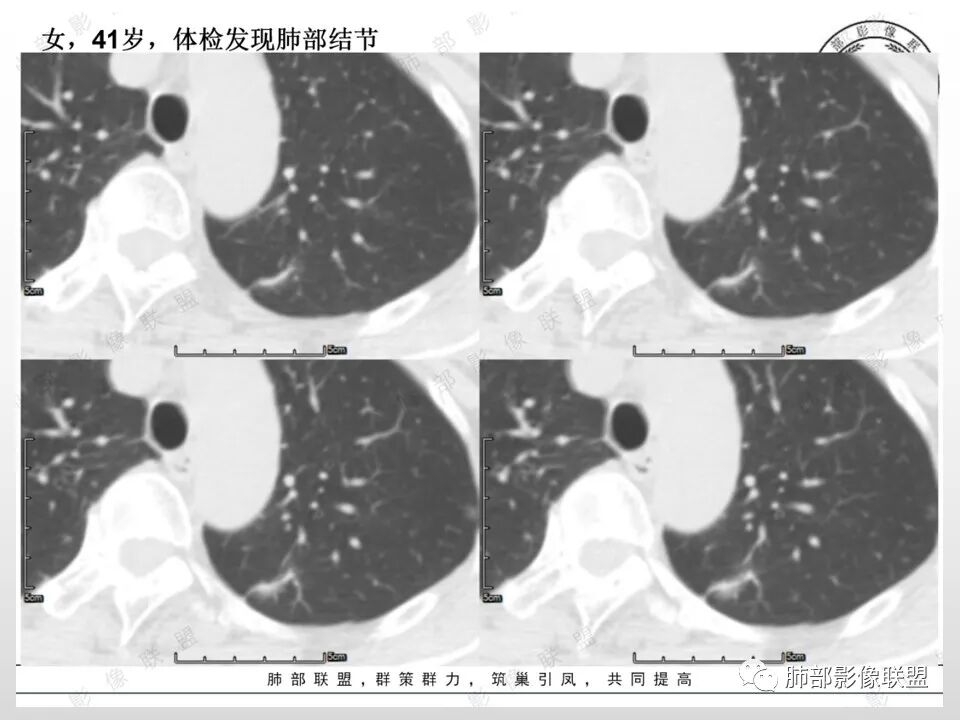

高强化,实性结节,边缘有磨玻璃,有膨隆,斜裂侧偏平直胸膜凹陷,IAC,鉴别炎性肉芽肿

左肺上叶长条状病灶,胸膜牵拉,边缘平直,磨玻璃边界清楚,不均匀强化,考虑炎性,不完全排除肺癌

左肺结节,形态不规则,边缘略收缩,分叶,部分边缘平直,周围可见清晰磨玻璃影,增强后明显强化,考虑:血管瘤,炎性假瘤,鉴别腺癌

中年女,左肺结节,边缘平直,明显持续不均匀强化,周围略毛糙,考虑IMT

中年女性,左肺上叶长条状病灶,宽基底与胸膜交界,胸膜凹陷,病灶边缘平直,局部收缩及膨隆,周围可见磨玻璃,其边界清楚,增强病灶不均匀强化,影像表现有炎性病变,也有明显占位表现,考虑OP,有膨胀性表现的小结节,不完全排除肺癌!需要结合相关检查。

混合磨玻璃,边界清,边缘凹陷,月牙铲,虽明显强化,还是先考虑腺癌,鉴别炎性肉芽肿或IMT等。

体检发现左肺上叶尖后段混合磨玻璃结节,考虑浸润性腺癌可能性大,建议抗感染后复查,明显强化有不支持的地方,左肺上叶尖后段外侧胸膜下小磨玻璃结节,提示AAH。

中年女性,查体发现左上肺条块结节,靠近斜裂,边缘平直有收缩,胸膜牵拉,明显强化,考虑炎性假瘤或炎性肉芽肿,鉴别腺癌。

中年女性,体检发现。左肺上叶后段不规则结节灶,密度不均匀,病灶周围可以边界似清非清毛玻璃影,临近胸膜牵拉,增强扫描病灶明显不均匀强化。考虑炎性假瘤,鉴别腺癌。

混合磨玻璃,边界清,分叶,收缩力强,月牙铲,胸膜凹陷,虽明显强化,还是先考虑腺癌,鉴别炎性肉芽肿。

左肺上叶尖后段实性结节,边缘有清晰磨玻璃,胸膜有牵拉凹陷,明显强化,CT值超过主动脉,考虑血管畸形(周围磨玻璃可能是出血),鉴别IAC(影像表现符合,强化不符)

混合密度结节,磨玻璃密度边缘清楚,考虑腺癌。

患者中年女性,体检发现。胸部CT:左肺上叶后段长条形结节灶,边缘光滑,边界清楚,见分叶、毛刺、胸膜牵拉及平直征象。增强明显强化,内可见血管增粗,综合考虑恶性病变,浸润性腺癌可能大,鉴别结核。

左上肺前后段不规则实性病灶,浅分叶,边缘部分平直收缩,轻微胸膜牵拉,伴周围磨玻璃样改变,强化明显,感觉是炎性恶性征像均有。

左肺上叶后段条片状影,边缘部分模糊,前缘平直后缘澎隆,周围可见大部分清晰的GGO,毛刺不明显,可见索条影,内密度不均可见条状低密度,增强除条状低密度外明显强化。支气管似见病灶边缘截断。考虑腺癌可能,抗炎治疗除外炎性肉芽肿。

1.中年女性,体检发现;2.左肺上叶后段长条形结节灶,边缘有膨隆,也有收缩,腺癌和炎性结节都可以,但是周围见边界清楚磨玻璃影强烈提示腺癌可能性。3.显著强化的肺结节,无论如何都应当引起我们的高度重视!尽管炎性病灶和新生物都可以,尽管强化程度不能作为诊断癌肿的依据。

★存在边界清楚的磨玻璃影,常常提示腺癌的可能性,尤其随诊复查没有变化。